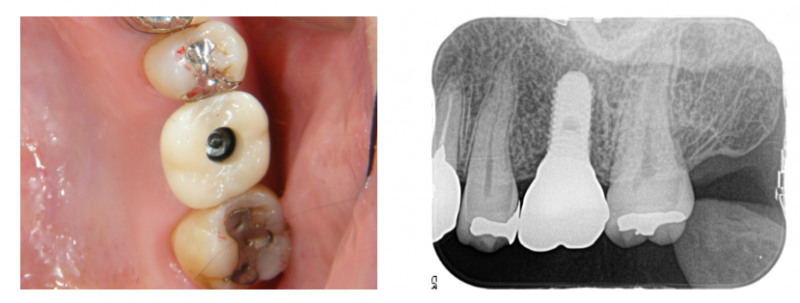

歯型を採って、歯冠を作ります。

インプラントと骨が結合したら、歯型を採って歯冠になる部分を作ります。

このケースはジルコニアという素材で作ります。表面がツルツルで汚れが付きにくいというメリットがあります。インプラント本体とは、ネジで固定します。

口腔内にセットしました。

ネジで固定するシステムですので、咬み合わせの面に穴が開いています。

このシステムにすることで、ネジの緩みに対応しやすく、着脱も専用の工具があれば自由です。

専用のレンチでネジを締めます。

基本的に、すべてのケースでこのシステムにします。

ネジ穴を白い詰め物でふさいで完成です。